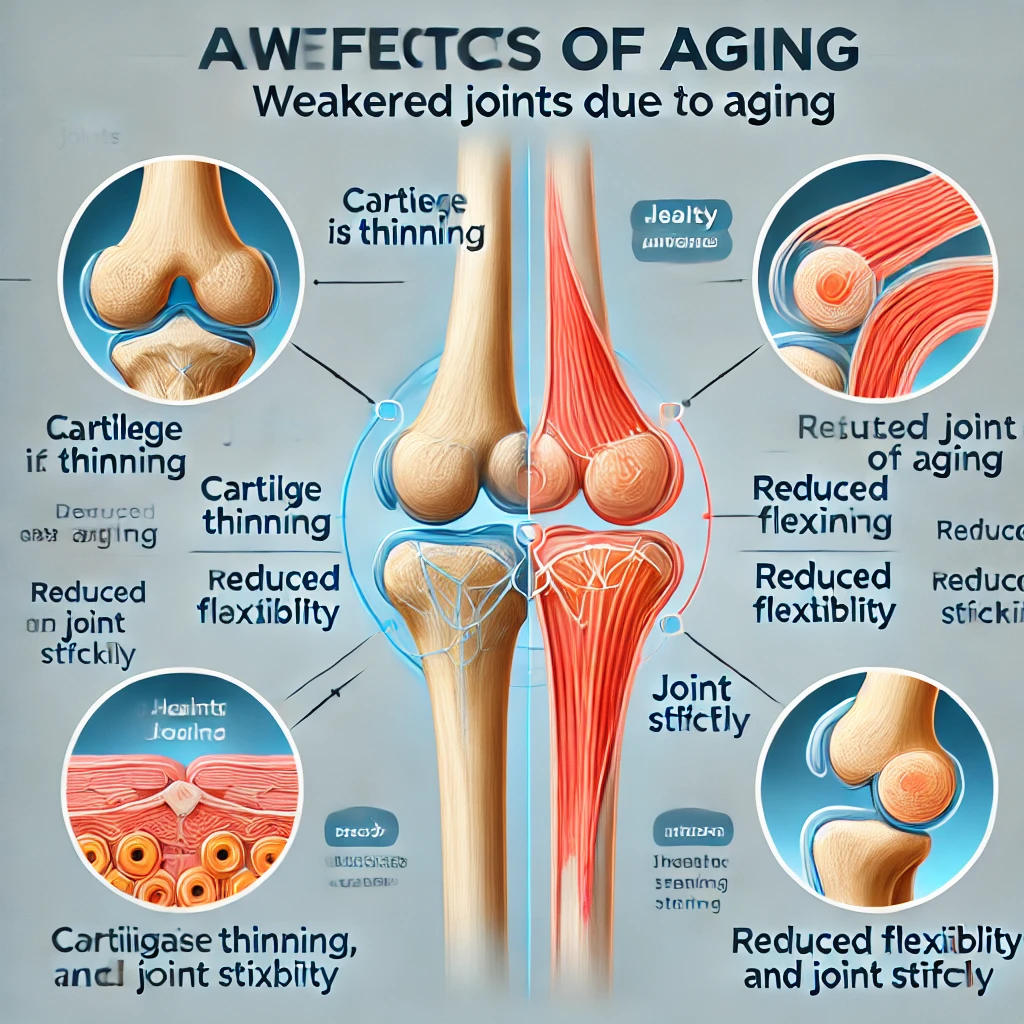

콘드로이친(Chondroitin)은 연골 조직의 주요 구성 성분 중 하나로, 주로 관절 건강을 지키는 데 중요한 역할을 합니다. 특히 나이가 들면서 연골이 손상되고 관절이 약해지는데, 이때 콘드로이친은 연골 조직의 회복을 촉진하고 염증을 억제하여 통증을 완화시켜 줍니다.

콘드로이친은 관절의 윤활제 역할을 하여 관절의 움직임을 부드럽게 만듭니다. 이는 특히 나이가 들면서 관절이 뻣뻣해지는 중장년층에게 큰 도움이 됩니다.

장기적으로 사용하면 연골 손상을 방지해 관절 질환의 진행을 늦추는 데 도움이 됩니다. 만성적인 관절염 환자들에게 유용할 수 있습니다.